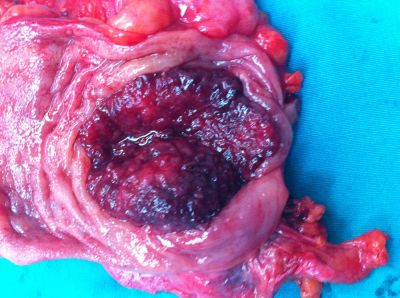

Χειρουργικό παρασκεύασμα εγκάρσιου κόλου. Διάνοιξη του τοιχώματος, και αποκάλυψη του καρκίνου που αποφράσει πλήρως τον αυλό του εντέρου.

Μετά την διάνοιξη του τοιχώματος του εντέρου, ανευρίσκεται η καρκινική μάζα του αποφράσει πλήρως τον εντερικό αυλό.